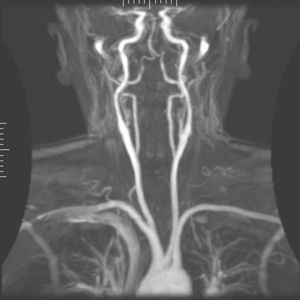

تصوير الأوعية بالرنين المغناطيسي

تصوير الأوعية بالرنين المغناطيسي (MRA)، هي مجموعة من التقنيات تستخدم التصوير بالرنين المغناطيسي لتصوير الأوعية الدموعية. ويستخدم تصوير الأوعية بالرنين المغناطيسي للحصول على صور للشرايين in order to evaluate them for stenosis (abnormal narrowing), occlusion or aneurysms (vessel wall dilatations, at risk of rupture). MRA is often used to evaluate the arteries of the neck and brain, the thoracic and abdominal aorta, the renal arteries, and the legs (called a "run-off").

MRA has been successful in studying many arteries in the body, including cerebral and other vessels in the head and neck, the aorta and its major branches in the thorax and abdomen, the renal arteries, and the arteries in the lower limbs. For the coronary arteries, however, MRA has been less successful than CT angiography or invasive catheter angiography. Most often, the underlying disease is atherosclerosis, but medical conditions like aneurysms or abnormal vascular anatomy can also be diagnosed.

An advantage of MRA compared to invasive catheter angiography is the non-invasive character of the examination (no catheters have to be introduced in the body). Another advantage, compared to CT angiography and catheter angiography, is that the patient is not exposed to any ionizing radiation. Also, contrast media used for MRI tend to be less toxic than those used for CT angiography and catheter angiography. The greatest drawbacks of the method are its comparatively high cost and its somewhat limited spatial resolution.